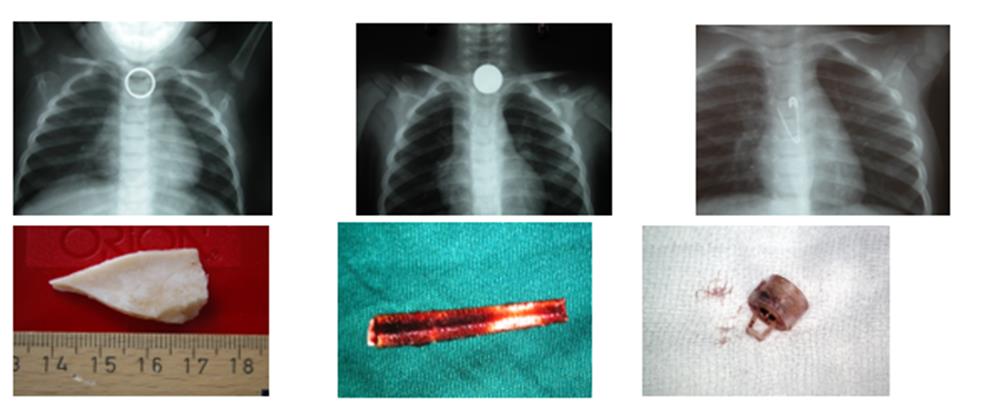

Οι εισροφήσεις ξένων σωμάτων σε παιδιά μέχρι 4 ετών, είναι δυστυχώς συχνές. Από μια μελέτη που έγινε από τις Παιδο-ωτορινολαρυγγολογικές κλινικές όλων των Δημόσιων Παιδιατρικών Νοσοκομείων της χώρας, από το 1995 έως το 2015, έγιναν 4.127 βρογχοσκοπήσεις για αφαίρεση ξένων σωμάτων του πνεύμονα σε παιδιά με εντυπωσιακή ποικιλία όσον αφορά και στο μέγεθος και στην υφή αυτών. Εικόνα 3.

HGG - ΚΟΥΔΟΥΜΝΑΚΗΣ ΕΜΜΑΝΟΥΗΛ

(Εικόνα 3)

Τα ξένα σώματα οισοφάγου δεν βάζουν σε κίνδυνο τη ζωή του παιδιού όπως τα ξένα σώματα του πνεύμονα και είναι πιο σπάνια. Η ίδια μελέτη που έγινε από τα Δημόσια Παιδιατρικά Νοσοκομεία κατέδειξε στο ίδιο χρονικό διάστημα 784 οισοφαγοσκοπήσεις  για ξένα σώματα στον οισοφάγο.